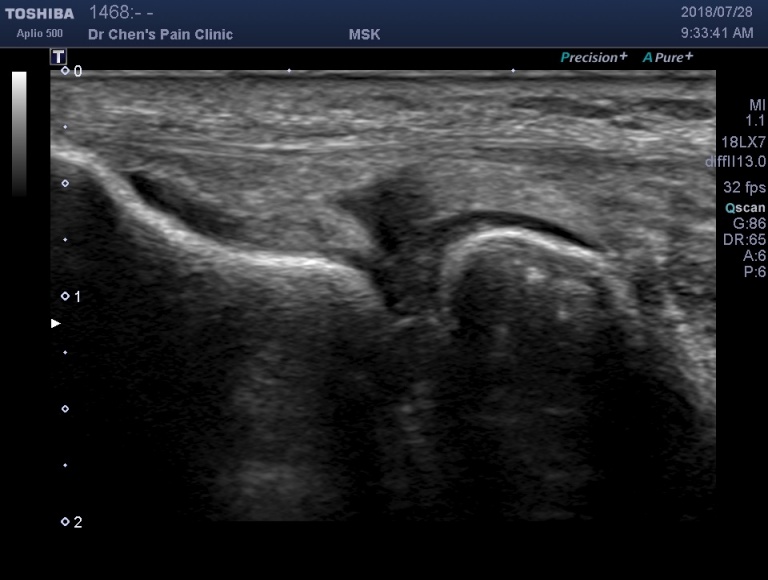

超音波診斷

彩色超音波可以清楚地顯示出發炎比較明顯的位置